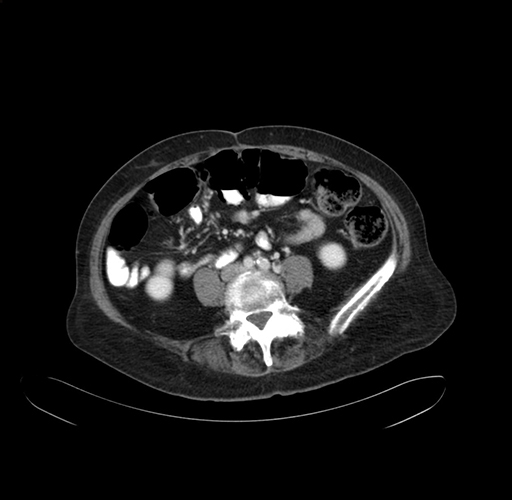

Pre-Chemo: Axial Venous

Axial Venous